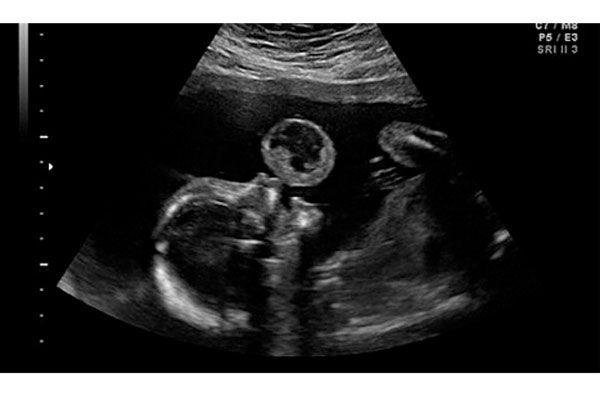

Los cirujanos fetales de la Universidad de Miami y del Jackson Memorial Hospital, Ruben Quintero y Eftichia Kontopoulos, informaron que la operación de poco más de una hora se efectuó en 2010 y lograron cortar el tumor al feto con un láser mientras la madre estuvo bajo anestesia local.